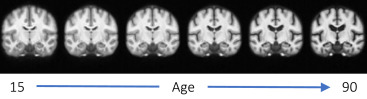

图1.AtlasMorph开发的条件模板,作为年龄的函数。